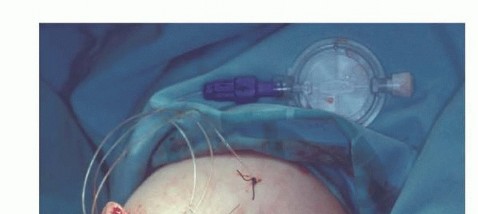

TECH FIG 4 • (continued) E. Closed surgical wound over an epineural catheter which provides continuous flow of local analgesics was installed into the nerve sheath to control postoperative pain.

A rigid dressing is applied immediately postoperatively to decrease pain and edema and facilitate maturation of the stump (FIG 7). Care must be taken to adequately protect the skin that directly overlies the bone.Stump edema is rarely a significant problem in the upper extremity, and prosthesis training should begin as soon as possible after surgery.Continuous suction is required for 3 to 5 days, and perioperative intravenous antibiotics are continued until the drainage tubes are removed.Active and passive ranges of motion around the shoulder and elbow (if exists) are practiced as tolerated.

Wound dehiscence Deep infectionLoss of elbow motion (when above-elbow amputation is done) Phantom limb pain FIG 7 • A rigid dressing is used to decrease postoperative pain and edema: (A) above-elbow amputation and (B) below-elbow amputation.